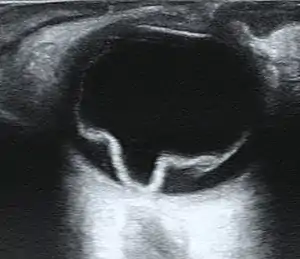

Ultrasound of a retinal detachment in a patient presenting with complete vision loss and light perception only.

Ultrasound, MRI, and CT scan are commonly used to diagnose retinal detachment.